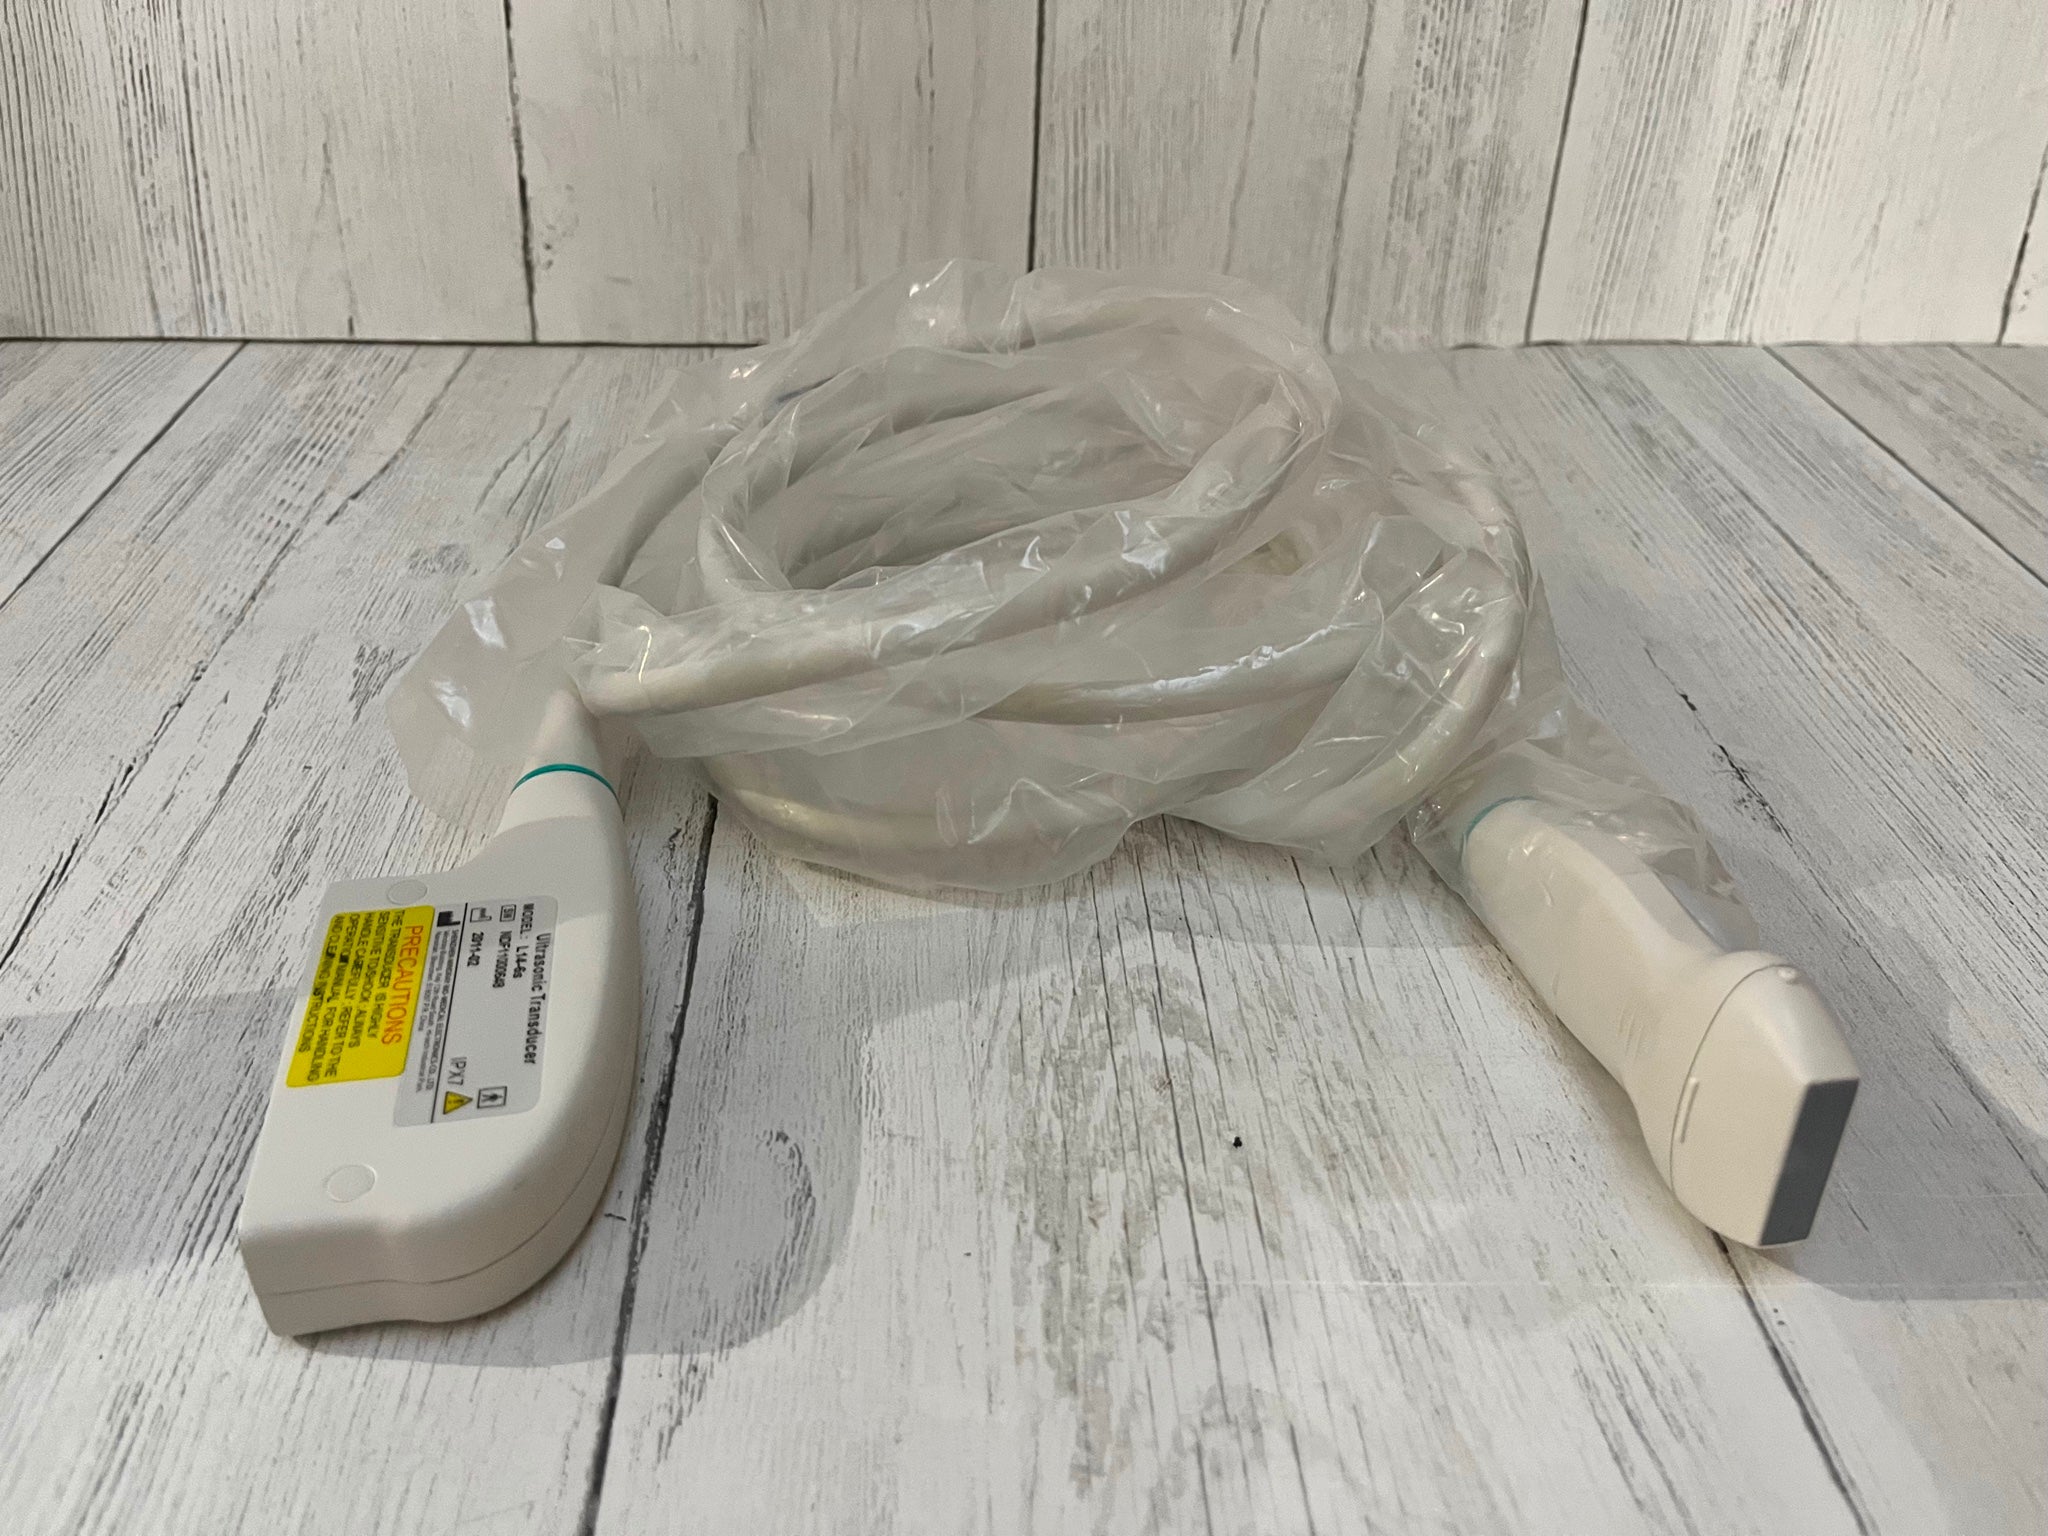

Optional: Convex probe 3.5MHz: Linear probe 7.5MHz/Transvaginal probe 6.5MHz

The Laptop LCD Digital 10.1-Inch Ultrasound Scanner is designed for high-quality imaging. This portable device offers detailed visuals, allowing healthcare professionals to deliver accurate diagnoses effortlessly. Equipped with both convex and transvaginal probes, it enhances versatility in various medical procedures. Its compact design ensures that you can carry it easily between locations, making it an essential tool for any medical practice. The user-friendly interface further simplifies operation, so you can focus on patient care without unnecessary distractions.